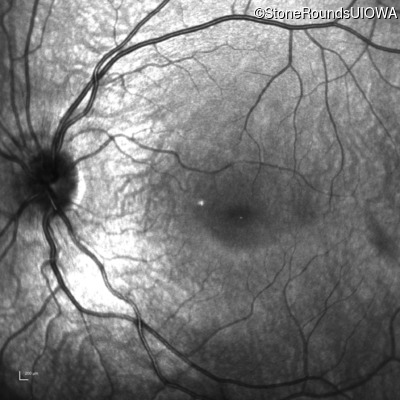

Age at visit: 7 years

This 7 year old boy had nystagmus first noticed at 4 months of age.

Age at visit: 10 years

Age at visit: 11 years